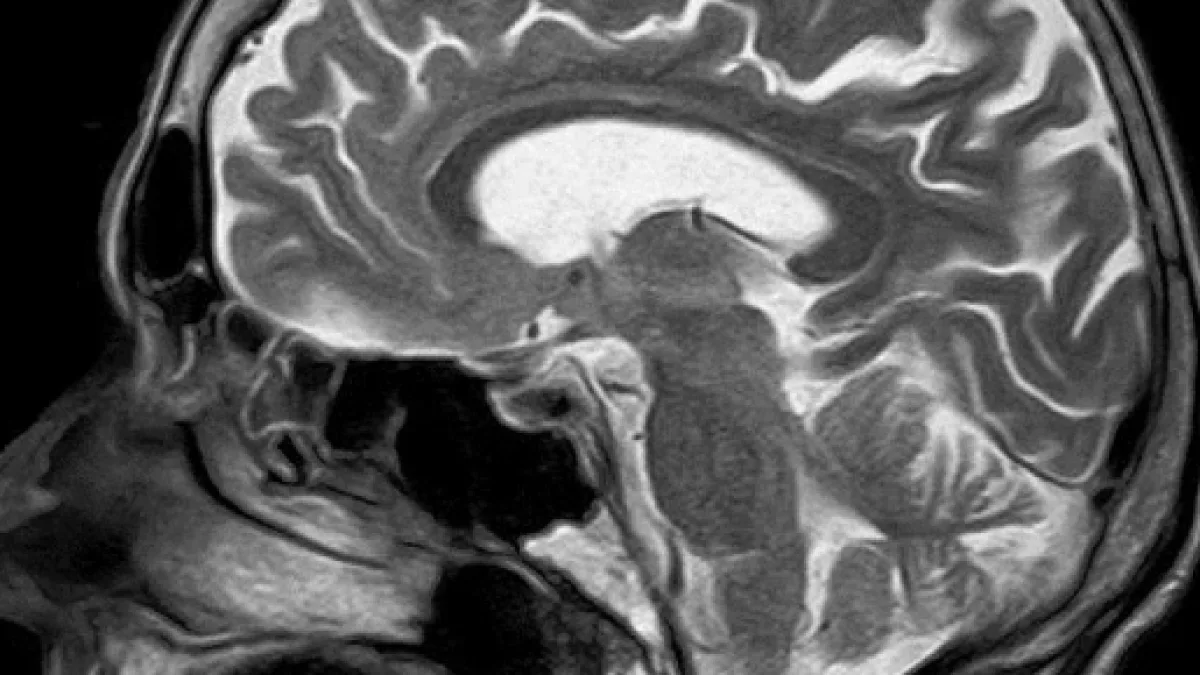

Se dice que una persona tiene un tumor en el cerebro cuando hay un incremento canceroso dentro del cerebro. El tumor maligno de un cáncer de cerebro afectará algunas funciones del cerebro, según el lugar donde se encuentre.